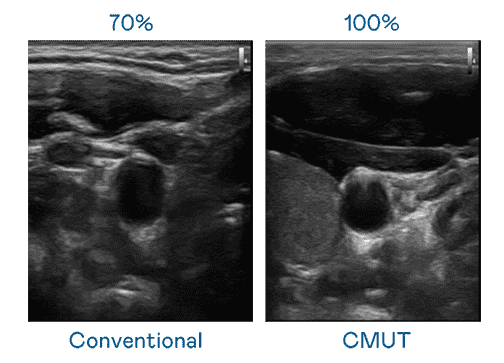

CMUT 技术是一种用电容式微机电元件来产生超音波讯号的技术。。。。与传统 PZT 压电式技术相比,,CMUT 频宽增加 30%,,,更宽频的超音波讯号让影像解析度大幅提升,,,是实现高影像品质医疗超音波扫描、、、、促进精准医疗发展的关键技术。。

超音波影像的解析度高低,,,首先取决于探头能发出的讯号频宽。。。Wepay CMUT 可提供高清晰的超音波讯号,,提供高频宽、、、、高灵敏度、、、、影像纹理细节更高的超音波影像,,协助医护人员缩短影像判读时间及利用精准的医疗影像进行诊断。。。。